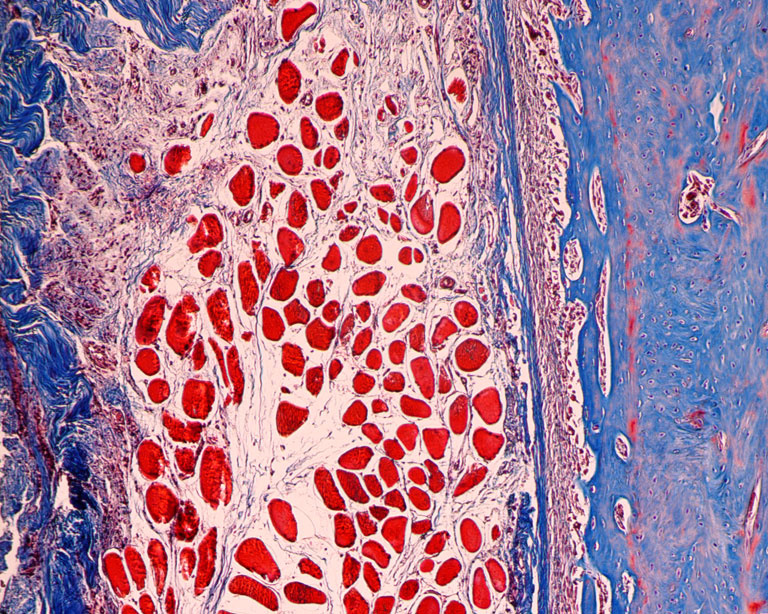

"The fundamental question that we are trying to answer is can we harness the body’s own cells to repair or regenerate human tissue, in cases where it may not be possible without treatment. In this work, we are tailoring nanotherapies that can be used to direct cells to for bone tissue. The images submitted here depict the living bone tissue environment at the microscopic level that is highly dynamic.

Materials that make up the bone, such as collagen (in blue) can be observed. Different cell types are observed including bone forming cells (osteoblasts – large single rounded structures embedded in the bone), bone marrow stem cells and hematopoietic stem cells in the bone marrow (which go on to form white blood cells) can be also be seen, which are smaller rounded structures clustered together. Also depicted in the image is the organized structural diversity of the bone, which can be spongy (web-like) or compact (plate-like)."